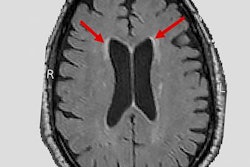

Goyal and colleagues analyzed data from 121 female and 84 male cognitively normal adults (age range, 20-82 years) participating in six different studies at the institution. All subjects underwent metabolic brain PET and structural 3-tesla MRI scans. PET images were coregistered to individual T1-weighed MR imaging sequences and regional measurements of total glucose and oxygen consumption in various brain regions. The glucose information is particularly key to the study because the brain runs on sugar, and how the brain uses that sugar changes as people age.

The researchers first trained the machine-learning algorithm by inputting data on the men's ages and brain metabolism. Next, they entered the women's brain metabolism data and directed the algorithm to calculate each woman's brain age. They found that the women's brains were an average of 3.8 years younger than their chronological ages. This relative youthfulness was observed even among study participants in their 20s.